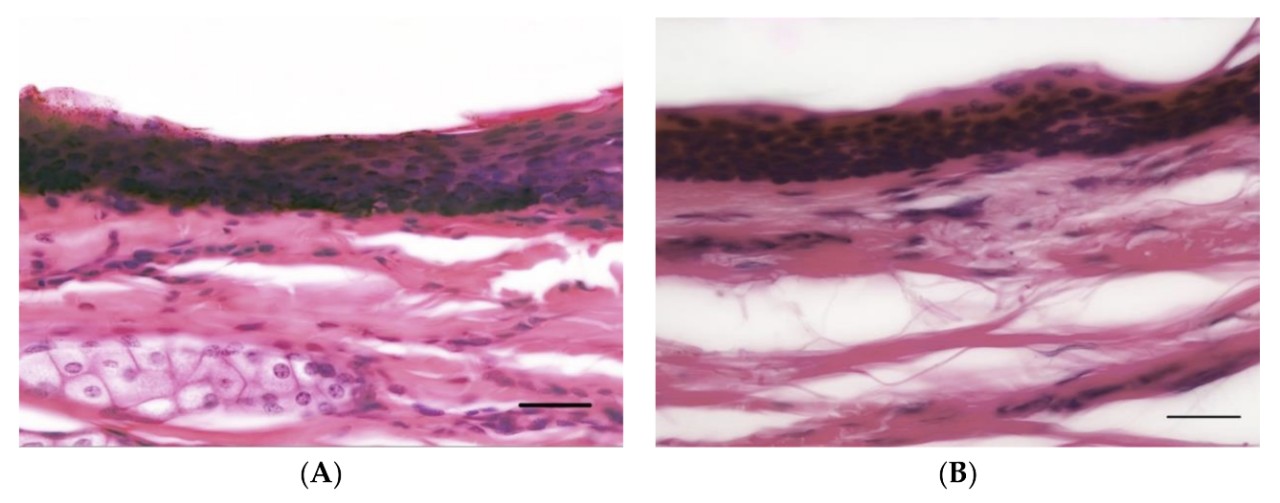

Images of horse (A) and human (B) skin, showing comparable epidermal thickness.

Professor McGreevy and colleagues examined whether horses are likely to feel as much pain as humans would when whipped. Using microscopic samples of skin from 10 deceased humans and 20 euthanised horses, they looked for differences between the species’ skin structure and nerve supply.

The results revealed “no significant difference” between humans and horses in the concentration of nerve endings in the outer layers of skin, nor any difference in thickness of this skin layer.